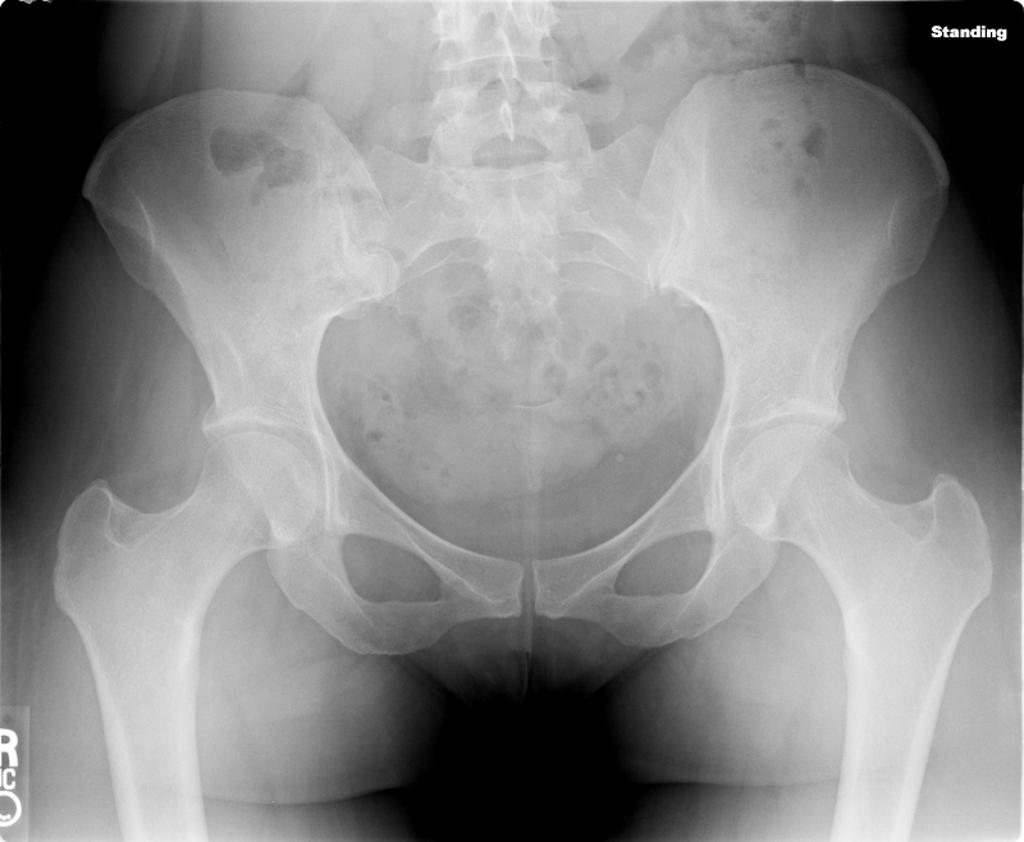

Pelvis x-ray for the case: